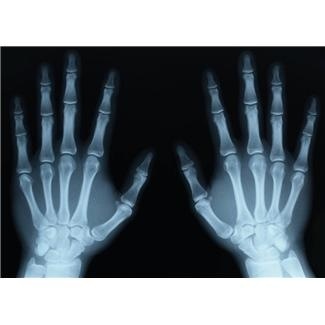

X-ray are essentially a type of photograph and are admissible if:

1.The x-rays are authenticated, and

2.The x-ray technician’s competence is shown.

The sponsoring witness must establish that the x-ray is a “true and accurate representation of the evidence portrayed.” Lewis v. State, 730 N.E.2d 686, 690-691 (Ind. 2000), citing to, Labelle v. State, 550 N.E.2d 752, 754 (Ind. 1990); Lewis v. State, 730 N.E.2d 686, 691 (Ind. 2000). In this regard, if the x-ray is shown to have been taken by a regular x-ray technician in a hospital, no further showing of the technician’s qualifications or the machine’s reliability is necessary. Howard v. State, 264 Ind. 275, 342 N.E.2d 604, 608–609 (1976). Typically, the doctor ordering the x-rays is familiar with the group takiing the x-rays and is able to vouch for their competency and reliability.